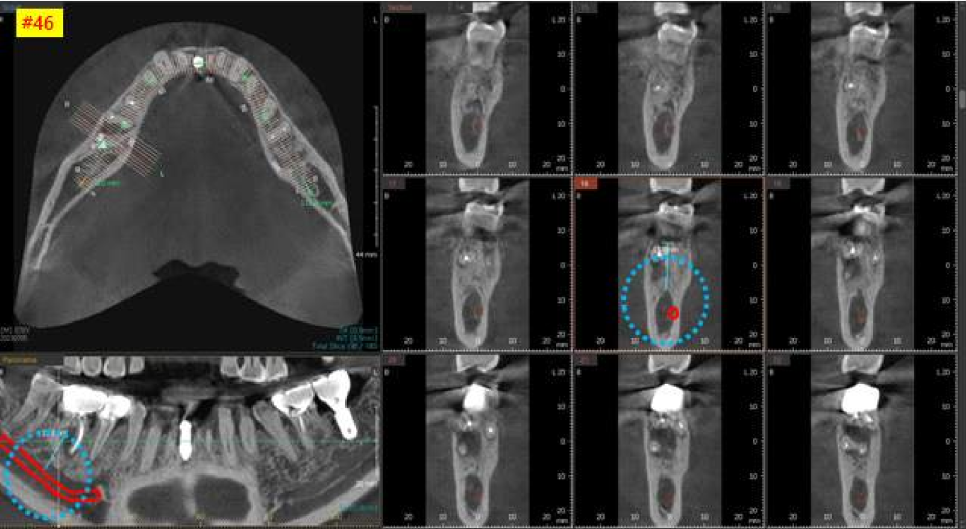

다음 오른쪽 아래 어금니의 3차원 CT 사진입니다.

보시면 까맣게 뼈가 녹아 있는 상태를 볼 수 있습니다.

치아 뿌리를 잡아주는 치조골이라는 뼈가

계속 염증으로 인하여 녹고 있는 상태입니다.

염증을 깨끗하게 제거하고

뼈이식을 같이 하기로 결정했습니다.

역시, 인접치 관계를 고려해서,

가장 이상적이고 안전한 위치를 찾아

적정한 두께와 길이의 임플란트를 선택했습니다.

3차원 CT사진에서 빨간색으로 표시해놓은 신경관을

피할 수 있도록 CT를 분석하고

이에 맞는 직경과 길이의 임플란트를 선택하여

수술을 시작하였습니다.